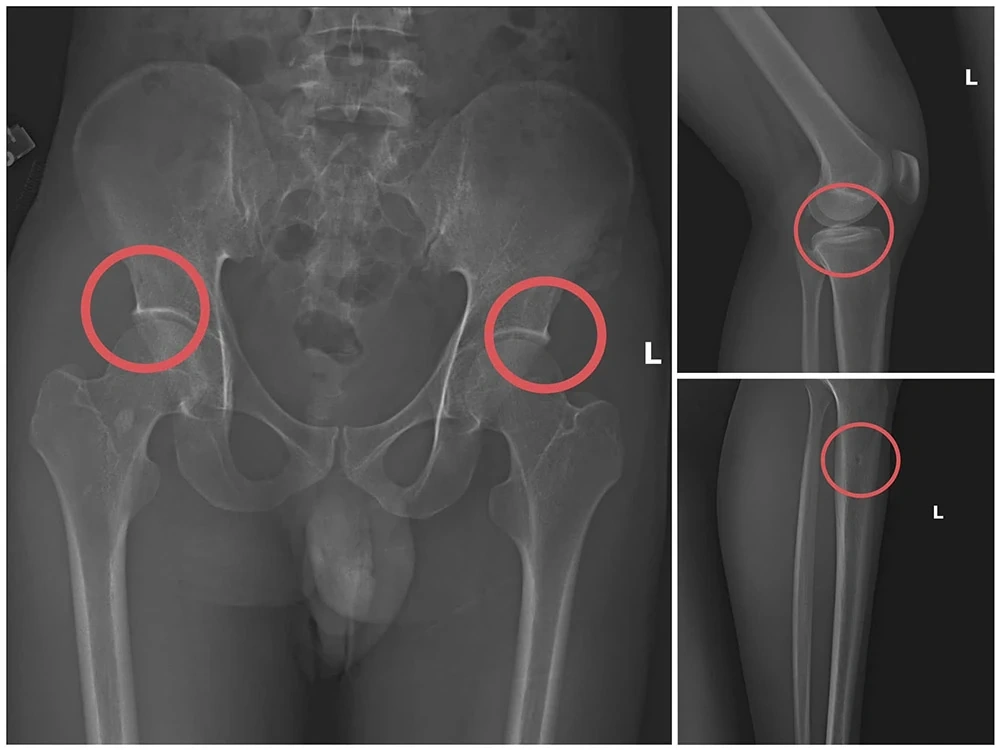

Bản phim chụp XQ một số tổn thương xương do đối tượng tạo ra

Đáng chú ý, Châu trực tiếp thực hiện hành vi tiêm thuốc mê rồi dùng kim tiêm, búa, đinh tác động vào xương người mua bảo hiểm, tạo nên các vết nứt, vỡ xương tương tự tai nạn thật. Khi thương tích đã tạo xong, Châu tiếp tục hướng dẫn các đối tượng dựng hiện trường giả như điện giật ngã, trượt chân ngã suối, nhằm hợp thức hóa bệnh án và hoàn thiện hồ sơ yêu cầu chi trả.

Thông qua các tài liệu thu thập được, Cơ quan Cảnh sát điều tra đã làm rõ đối tượng Tạ Minh Châu, sinh năm 1995, nguyên cán bộ Trung tâm Y tế huyện Cẩm Khê là kẻ chủ mưu, cầm đầu. Lợi dụng thời gian dài công tác trong ngành y và am hiểu sâu cấu tạo xương khớp, cũng như cơ chế chi trả bảo hiểm đối với các thương tích gãy xương có giá trị cao, Châu đã dựng lên một quy trình trục lợi bài bản, từ việc vận động mua bảo hiểm, tổ chức gây thương tích, đến hợp thức hóa hồ sơ bệnh án để chiếm đoạt tiền của các công ty bảo hiểm.

Theo đánh giá của đồng chí Giám đốc công an tỉnh, đây là thủ đoạn này vừa tàn nhẫn, vô nhân tính, coi thường sức khỏe, tính mạng của người tham gia, vừa được tính toán kỹ để gây thương tích đúng vị trí có mức chi trả cao, khiến các công ty bảo hiểm khó phát hiện dấu hiệu gian dối.